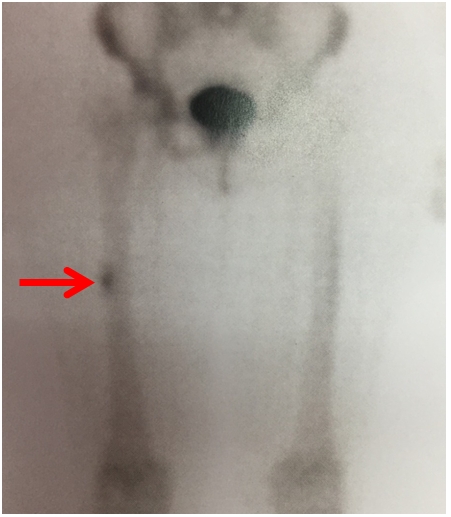

Gammagrafía ósea: permite evaluar la presencia de hiperemia focal en huesos y médula, pero con menor especificidad que la RMN o la TAC

A esta paciente se le solicitó una gammagrafía ósea

Fijación del trazador en sector cortical de diáfisis media de fémur derecho probablemente en relación con micro-fractura a dicho nivel

Se debe continuar con la actividad reducida hasta que no se detecte edema óseo en la RMN o no se detecte hipercaptación en la gammagrafía ósea.